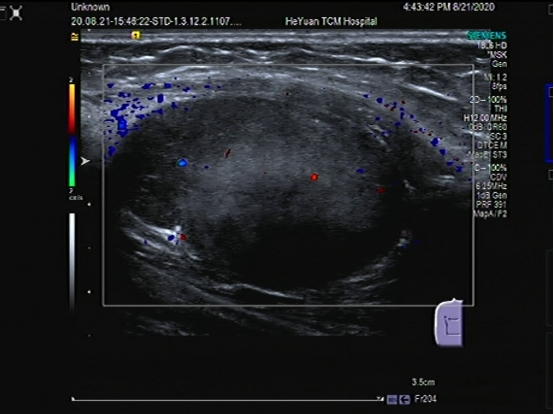

脂肪瘤、血管瘤、腱鞘囊肿等软组织肿物,肌骨超声可以确定肿物的性质、大小和位置。

↑典型牛奶咖啡斑

↑神经纤维瘤病